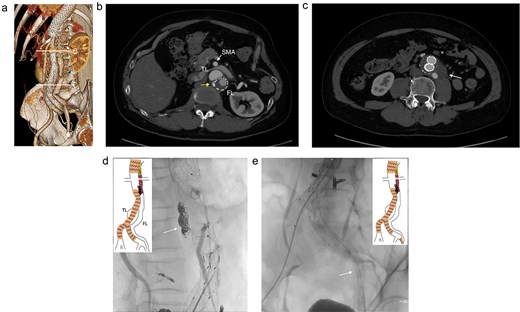

A 46-year-old man, with a history of noncompaction cardiomyopathy, underwent emergency zone 3 thoracic endovascular aortic repair (TEVAR) using TAG (WL Gore & Associates, Newark, DE, USA) for complicated type B acute aortic dissection. Postoperative contrast-enhanced computed tomography (CT) imaging showed the FL began from the descending aorta and extended into the left external iliac artery (EIA) (Fig. 1a), and several residual re-entries at the renal artery level (Fig. 1b) and one at the left EIA level. Both renal arteries were also originated from the true lumen. Both the FL and the post-dissection TAAA were dilated to diameters of 23 and 53 mm, respectively (Fig. 1c). Considering impaired cardiac function with the ejection fraction of 24%, the endovascular treatment was performed with intimal tear closure using FL stent graft placement as previous study reported [1]. First, endovascular aortic repair (EVAR) was completed with Excluder Aortic Extender (WL Gore & Associates, Newark, DE, USA) below the renal artery, followed by Excluder main body (WL Gore & Associates, Newark, DE, USA) landing on bilateral common iliac arteries. This excluded abdominal aortic aneurysm. Second, we placed a 10 × 40 mm Epic vascular self-expanding stent (Boston Scientific, Marlborough, MA, USA) in the FL at the level of distal end of the TAG. Then, the intimal tears at the renal artery level were closed using Endurant II iliac leg (cat No. ELW1624C94 Medtronic, Dublin, Ireland) from the FL side, overlapping with Epic stent proximally, and Aortic Extender distally (Fig. 1d and e). The retrograde angiography from left femoral artery sheath showed residual blood flow blowing up into the FL from the re-entry at the left EIA, and some lumbar arteries originating from the FL were contrasted.

Preoperative CT 3D reconstruction showing the FL extended from the descending aorta to the external iliac artery (a), contrast-enhanced CT axial images at the renal artery level with an intimal tear (b; arrow), and the abdominal aortic aneurysm level (c), and the intraoperative angiography showing the FL were contrasted through intimal tear at the visceral segment (d), Endurant II iliac leg placed in the FL closing intimal tears near the renal artery (e; white arrow). TL: true lumen; FL: false lumen.